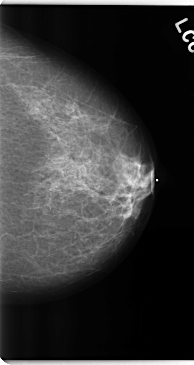

ics_version 1.0 filename C-0225-1 DATE_OF_STUDY 19 3 1997 PATIENT_AGE 55 FILM FILM_TYPE REGULAR DENSITY 2 DATE_DIGITIZED 14 4 1998 DIGITIZER LUMISYS LASER SEQUENCE LEFT_CC LINES 4744 PIXELS_PER_LINE 2512 BITS_PER_PIXEL 12 RESOLUTION 50 NON_OVERLAY LEFT_MLO LINES 4744 PIXELS_PER_LINE 2696 BITS_PER_PIXEL 12 RESOLUTION 50 NON_OVERLAY RIGHT_CC LINES 4736 PIXELS_PER_LINE 2728 BITS_PER_PIXEL 12 RESOLUTION 50 OVERLAY RIGHT_MLO LINES 4736 PIXELS_PER_LINE 2712 BITS_PER_PIXEL 12 RESOLUTION 50 OVERLAY |